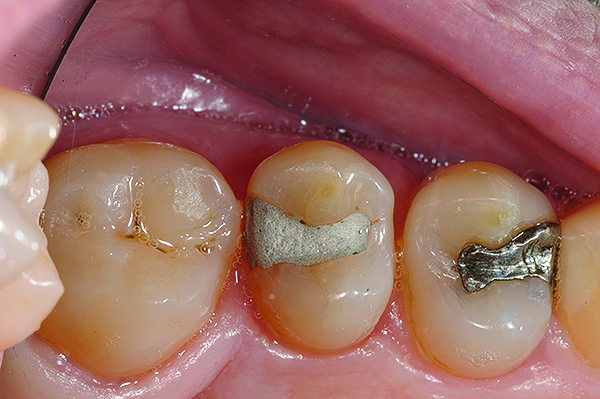

The case depicted in Figure 2 through Figure 5 was completed clinically in late 2009 and subsequently reported in a technique paper published by the author in 2010.37 The case describes the aforementioned EQUIA technique, which essentially employs a high-viscosity, posterior-grade GIC with a bulk-fill technique that is then surface-coated with a penetrating, nanofilled light-cured resin glaze. The reader is referred to the original paper for details about the case, materials, and technique. What is pertinent to this article, however, is the retention and continued durability of the restoration at approximately 42 months. Figure 2 and Figure 3 show the pretreatment view of defective Class I and Class V amalgam restorations, while Figure 4 and Figure 5 illustrate the 42-month recall of the EQUIA Fil restorations. Note that after nearly 4 years of clinical service both restorations were not only still in service but were in excellent condition and would be rated Alfa according to a modified US Public Health Service (USPHS) clinical rating criteria. There is clearly no evidence of excessive wear, staining, marginal microleakage, or recurrent decay. Though this single case is anecdotal, it supports the results found in more comprehensive clinical trials such as those referenced above.

Fig 4 and Fig 5. Occlusal (Fig 4) and buccal (Fig 5) 42-month recall views of the Class I and Class V GIC restorations placed with bulk-fill EQUIA technique.

Figure 4

Figure 5